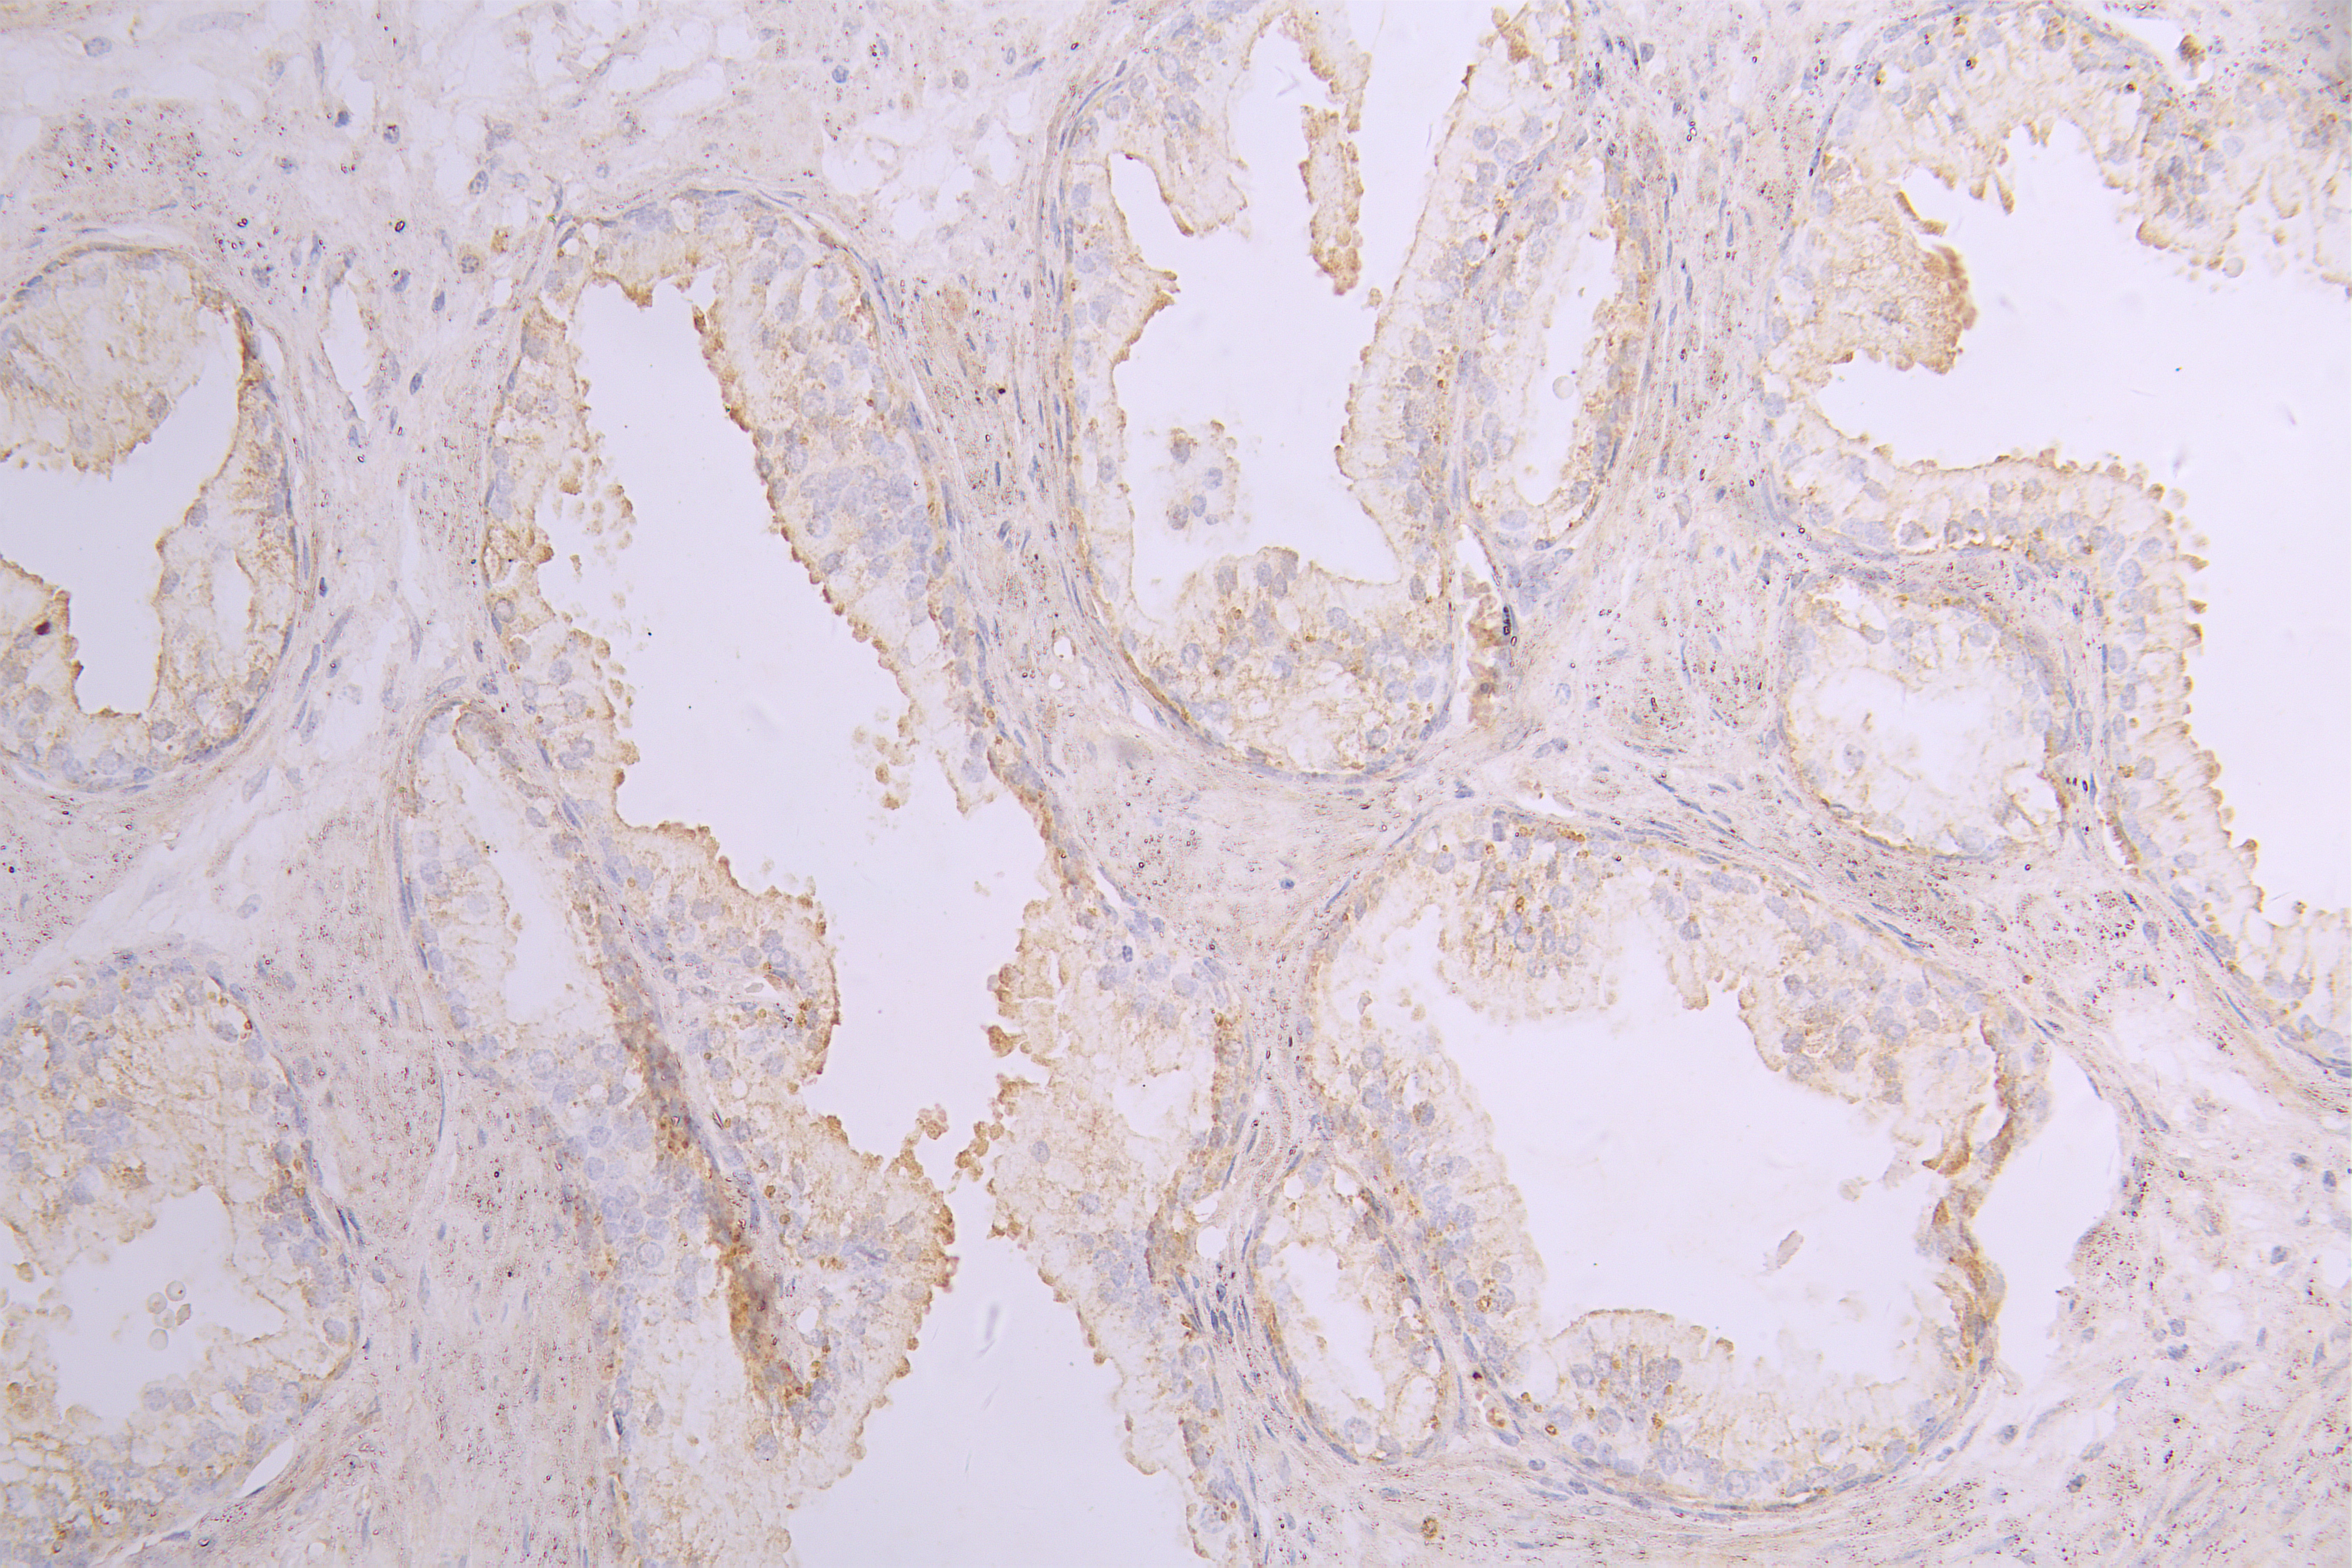

IHC image of CSB-RA859530MA1HU diluted at 1:100 and staining in paraffin-embedded human prostate cancer performed on a Leica BondTM system. After dewaxing and hydration, antigen retrieval was mediated by high pressure in a citrate buffer (pH 6.0). Section was blocked with 10% normal goat serum 30min at RT. Then primary antibody (1% BSA) was incubated at 4°C overnight. The primary is detected by a Goat anti-human polymer IgG labeled by HRP and visualized using 0.05% DAB.

Application Recommended Dilution IHC 1:50-1:200 -